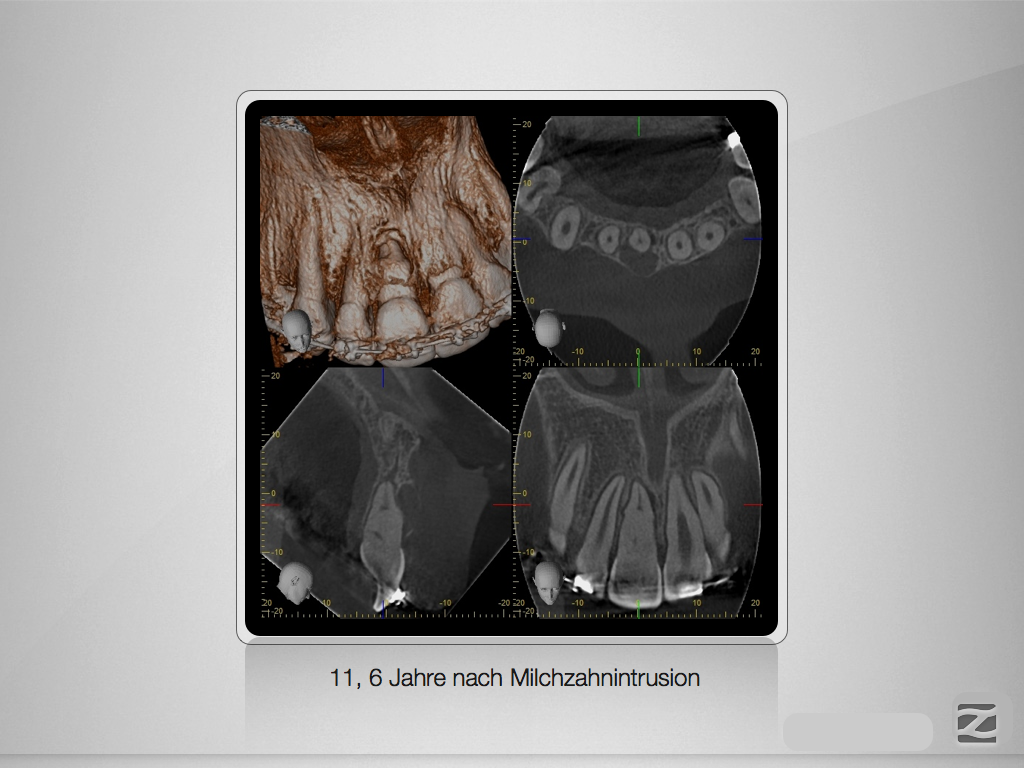

Spätfolge eines Milchzahn-Traumas